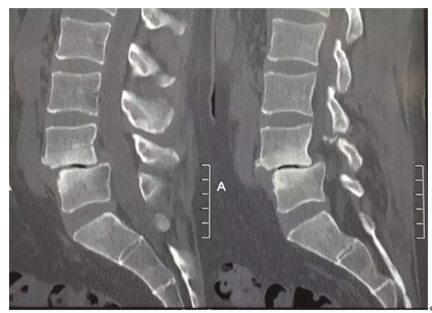

其实这就是一名腰椎滑脱患者X光片,可能还不是太明显,大家可以看下面这张图片。

图中的椎间盘之间明显已经发生错位,是不是光看着就忍不住想揉一揉自己的腰?或许此时已经有很多人想问了:“啥是腰椎滑脱?严重吗?需要手术吗?不会瘫痪吧?”今天,湘南学院附属医院疼痛科就带你了解一下腰椎滑脱。